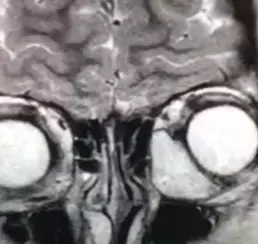

— На МРТ мы видим образование, которое находится под верхней стенкой глазницы, тесно примыкает к глазному яблоку и мышцам (см. рис. 10). Проводим трансконъюнктивальную орбитотомию и выделяем образование, тесно связанное с верхней косой мышцей (см. рис. 11). К сожалению, ее при выделении образования приходится пересечь. Иммуногистохимическое исследование подтверждает эмбриональную рабдомиосаркому, — рассказывает офтальмохирург. — Пациент продолжил лечение у онкологов. На данный момент он в ремиссии уже 3 года. Мы прооперировали его по поводу вертикального непостоянного косоглазия, которое развилось вследствие того, что мы резицировали часть верхней косой мышцы.

На МРТ видно, что новообразование состоит из двух частей, одна из которых кистовидная, а другая гипоэхогенна по отношению к мозговой ткани. Образование вызывает компрессию мышц глаза, смещает зрительный нерв.